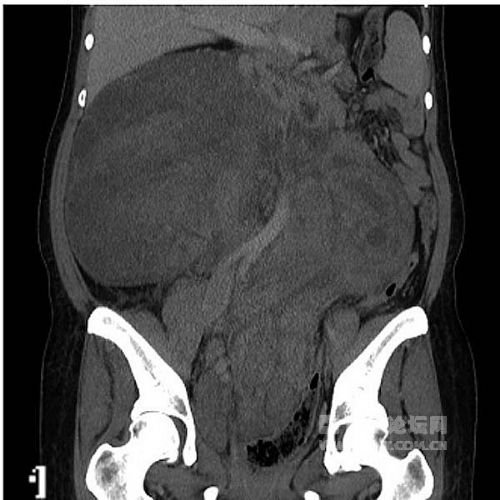

入院体格检查:神志清,皮肤、巩膜无黄染,全身浅表淋巴结未及肿大,腹隆,腹盆腔可扪及腹块,直径约30 cm,质地中等偏硬,边界清,活动度差,呈分叶状,局部压痛明显,余腹未及明显压痛、反跳痛,肝脾肋下未及,腹水征(-);直肠指检未及腔外肿块,指套无染血。

辅助检查:CT示腹盆腔巨大肿块;右侧髂静脉、下腔静脉、右心房及右心室瘤栓形成;右肾、双侧输尿管、膀胱、血管及消化道均受压推移。实验室检查示癌抗原125(CA125)为44.2 IU/ml,神经元特异性烯醇化酶(NSE)为17.0 ng/ml,雌二醇为1486 pmol/L。

放射科:该患者的CT及磁共振成像(MRI)检查显示,腹盆腔内有巨大不规则软组织密度影,边界不清,病灶推压临近肠管、胰腺、右肾及膀胱,右侧髂静脉、下腔静脉、右心房及右心室内可见充盈缺损影,考虑子宫平滑肌瘤病累及下腔静脉及右心房(图1~2)。